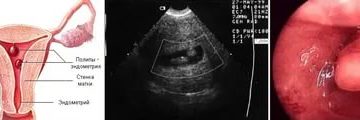

Изменения в месячных во время полипа и после его удаления Полип в матке или эндометрии…